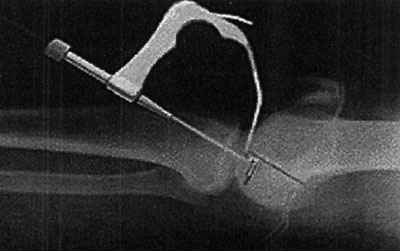

08_02_02_fig2

Luego de la liberación del remanente del LCA se labra túnel femoral y se coloca la guía de ingreso lateral para el tornillo Bone Mulch, la misma se utiliza a su vez para medir la longitud del tornillo.

08_02_02_fig3

Colocado el ligamento y luego de la fijación distal con una arandela multipunto y su respectivo tornillo, se coloca injerto óseo obtenido luego de la remoción de una camisa que se le coloca previamente a las mechas utilizadas para los túneles y destinada a tal fin. Al final del procedimiento se agrega una contratuerca al tornillo Bone Mulch que tiene como función evitar la migración del injerto óseo colocado y sirve a su vez para una futura revisión de la técnica.